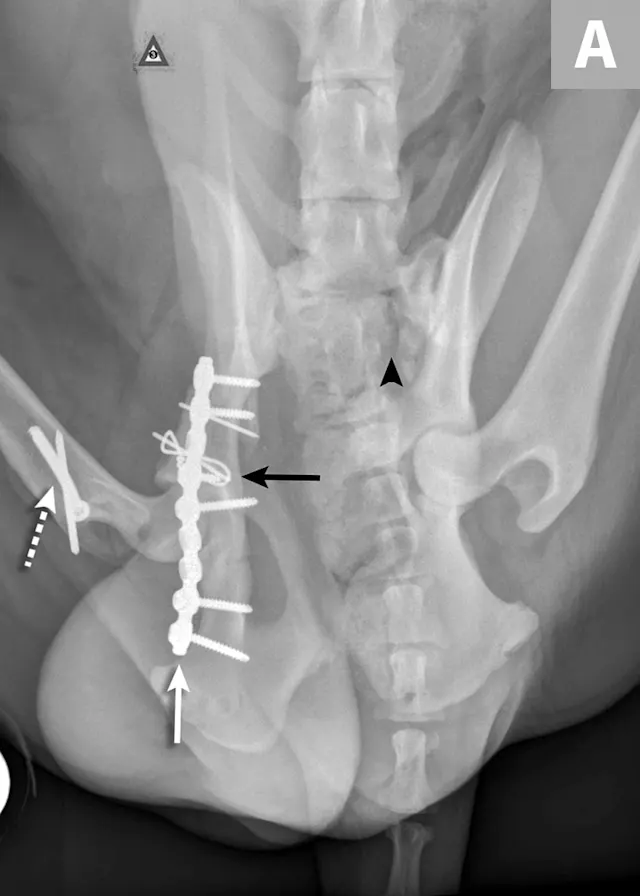

FIGURE 4A

Postoperative ventrodorsal (A) and lateral (B) projection images of the same dog in Figure 2. Fracture reduction was achieved with cross pins and a figure-eight hemicerclage wire (black arrows). Reduction was protected via application of a locking string-of-pearls neutralization plate (solid white arrows). To gain access to the full extent of the fracture, a greater trochanteric osteotomy was performed and stabilized with a positional screw and pin (dashed arrows). The ventrodorsal postoperative radiograph revealed a sacral fracture not previously appreciated (arrowhead). The fracture was successfully treated with conservative management.